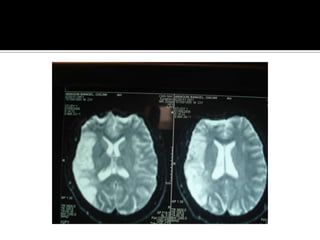

Caso clinico Mujerde 20 años , puérpera, llega a Hospital la catalogan como psicosis postparto. Dos días después coma y , después muerte cerebral. La TAC erróneamente fue interpretada como infartos lacunares.

Caso clinico Mujer de 20 años , puérpera, llega a Hospital la catalogan como psicosis postparto. Dos días después coma y , después muerte cerebral. La TAC erróneamente fue interpretada como infartos lacunares.

Trombosis Venosa CerebralCefaleaPapiledemaDeficitfocalCrisis epilepticasAlteracion de conducta

Trombosis venosa cerebralHEPARINAIV TROMBOLISIS ENDOVASCULAR TROMBECTOMIA ENDOVASCULAR